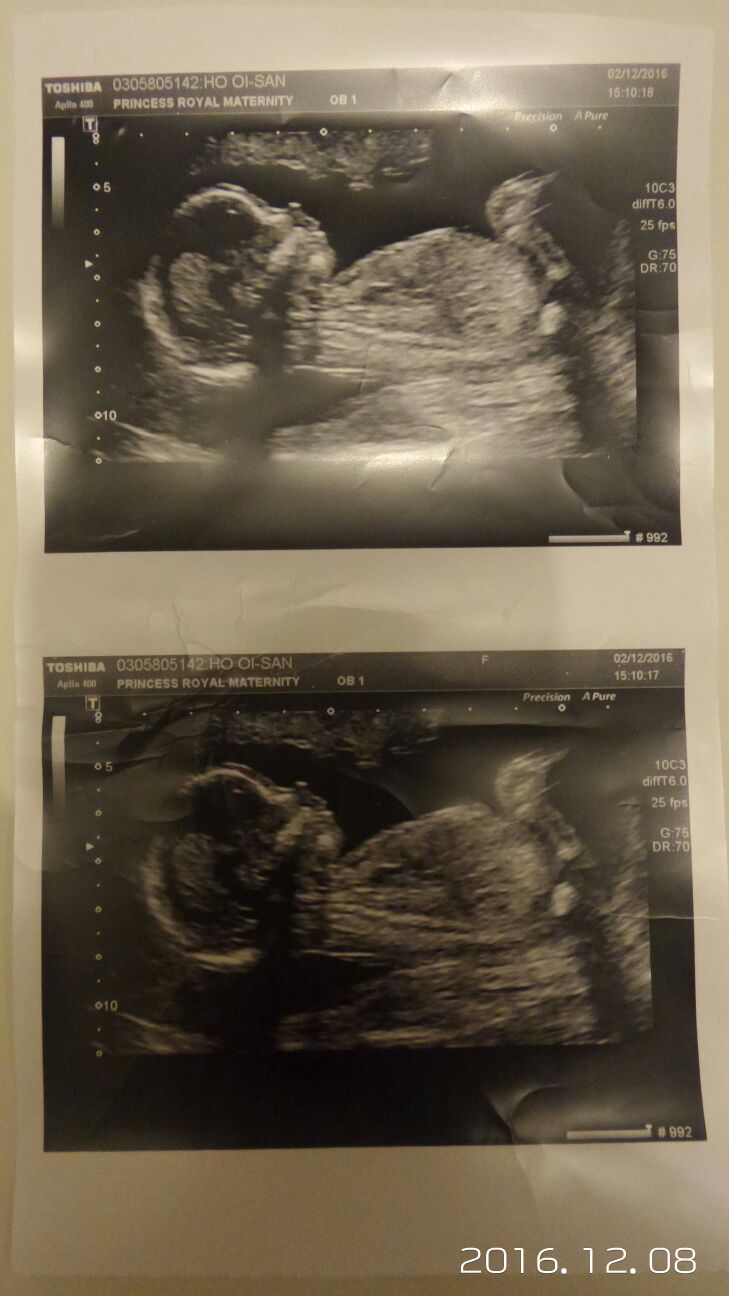

Am going girl also. The earlier photo in one there looks like a long flat white line parallel with the spine, indicates girl. There is also something under it that looks like a forked nub, which again would suggest girl. Not sure which is the nub but both indicate girl. Unless anyone thought it was stacking? But I don't think so x

The 16w one you wouldn't see a nub you'd need a potty shot